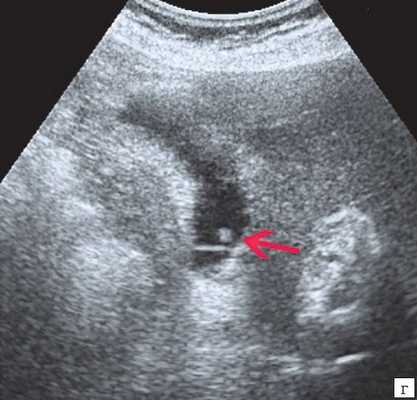

Специальную сверхтонкую струну-проводник удалось провести в сегментарный проток правой доли печени (рис. 2), после чего принято решение первоочередно расширить просвет протока специальными эндоскопическими бужами (рис. 3, 4), постепенно увеличивая диаметр последних.

Когда необходимый диаметр был достигнут, выполнено стентирование левого долевого желчного протока печени (рис. 5).

Через установленный ранее чрескожный дренаж проведено антеградное бужирование, а затем эндоскопическая установка второго стента в правый долевой проток печени (рис. 6-7).

После установки стентов в желчные протоки желчь естественным ходом поступает в двенадцатиперстную кишку, поэтому необходимость в наружном дренаже и постоянном приеме желчи отпадает.